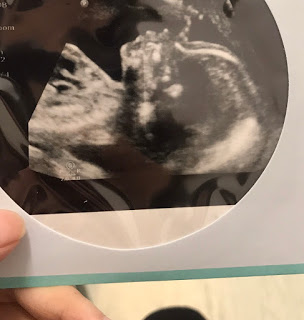

FINALLY~20周見到你個樣啦!!好激動!!因為20周既你扒係到訓,攪到媽媽照左個幾2個鐘